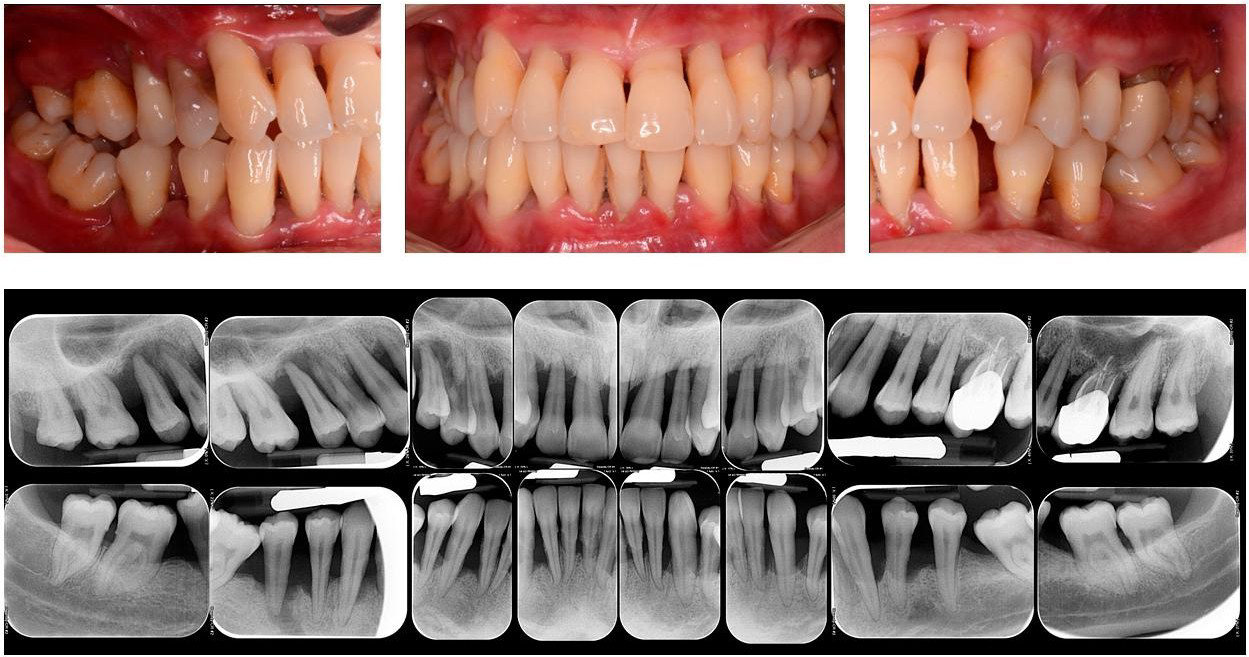

2. Periodontitis (Gambar 3). Periodontitis bersifat kronis dan progresif, serta dapat menyebabkan mobilitas hingga kehilangan gigi jika tidak mendapatkan perawatan yang berkelanjutan (1,4,5,6)

Gambar 3. Periodontitis (Peradangan pada jaringan penyangga gigi)5